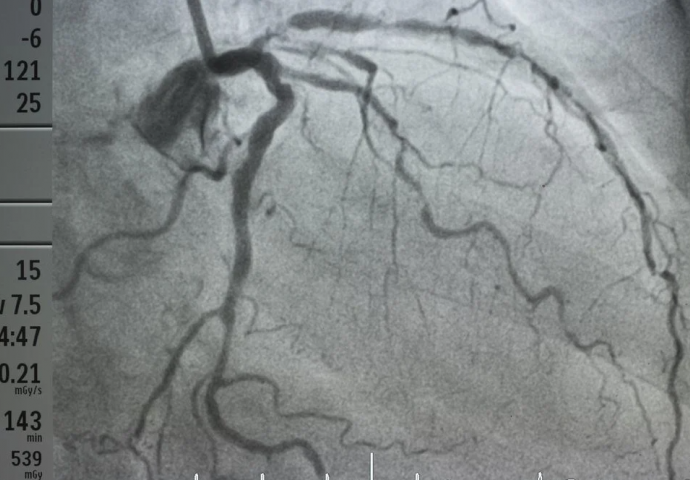

Mnogi imaju prepreke u arterijama već u dvadesetim godinama, a da toga nisu ni svjesni, sve dok ne bude prekasno. Od kritične je važnosti da prepoznate indikatore i budete oprezni kako biste što prije posjetili ljekara.

Ovo je lista najčešćih znakova začepljenih arterija. Ispitajte faktore rizika i promijenite svoju dnevnu rutinu radi vašeg zdravlja.

Začepljene arterije mogu izazvati nelagodu u nogama tokom aktivnosti poput hodanja. Ovo ukazuje na to da vaši udovi ne dobijaju dovoljno krvi. Nelagodnost u mišićima ili grčevi u nogama mogući su znakovi. Položaj ugruška ili začepljene arterije određuje lokaciju bola.

Smanjeni dotok krvi u srce izaziva nelagodu u grudima. Stezanje, utrnulost, težina, pritisak ili osjećaj peckanja neki su od simptoma. Pošto je to izazvano fizičkim ili emocionalnim naporom, ljudi obično ne primjećuju ove simptome.

Naše oči i mozak opskrbljuju karotidne arterije. Ako se ove arterije začepe, dolazi do prolaznog gubitka vida ili oštećenja vida na oku. Moždani udar je uzrokovan potpunom blokadom. Zbog toga je važno biti svejstan ovog upozorenja, prenosi Magazin Novosti.

Pored ova tri glavna simptoma, koja su najčešća, postoje i drugi propratni simptomi: umor, vrtoglavica, kratak dah, bol u krstima, hladne ruke ili noge, promjena boje kože u bolnom području.